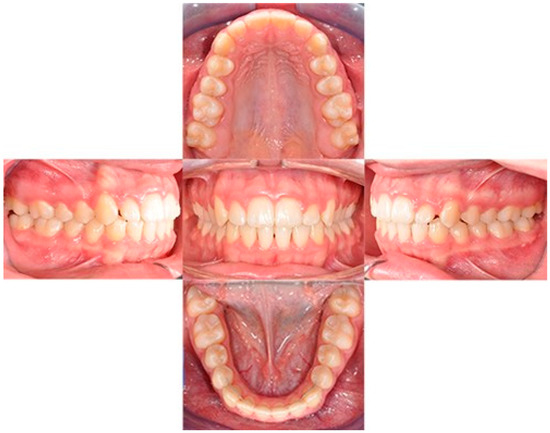

A 12-year-old girl with the second skeletal class (ANB 5), a high angle (FMA 27), and a facial index of 0.67 was selected. Soft tissue analysis showed a convex profile with a Z angle equal to 57 and an FMIA angle close to 55. The IMPA angle was 98. The analysis of the dental cast revealed a spee curve of 3.5 mm (Table 1). The occlusion presented a first molar class to the left, and a light second class to the right with 1 mm crowding in the lower jaw. The overjet was 0. The upper canines were impacted (Figure 1, Figure 2 and Figure 3). The patient’s chief complaint was altered aesthetic perception due to reduced dimensions of the deciduous canines. The treatment objectives were to retrieve space for upper canines’ eruption, level the spee curve, upright the lower incisors, and reduce the impact of the convex profile through occlusal vertical control to facilitate counterclockwise mandibular rotation.

Figure 1. Initial intraoral photos.